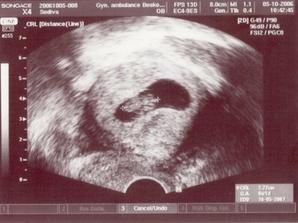

V srpnu jsme zjistili že čekáme miminko, měli jsme velikou radost že se povedlo brzy po svatbě. Ve dvacátém týdnu nám pan doktor potvrdil že to bude chlapeček, jméno jsme mu vybrali společnými silami - Martin...